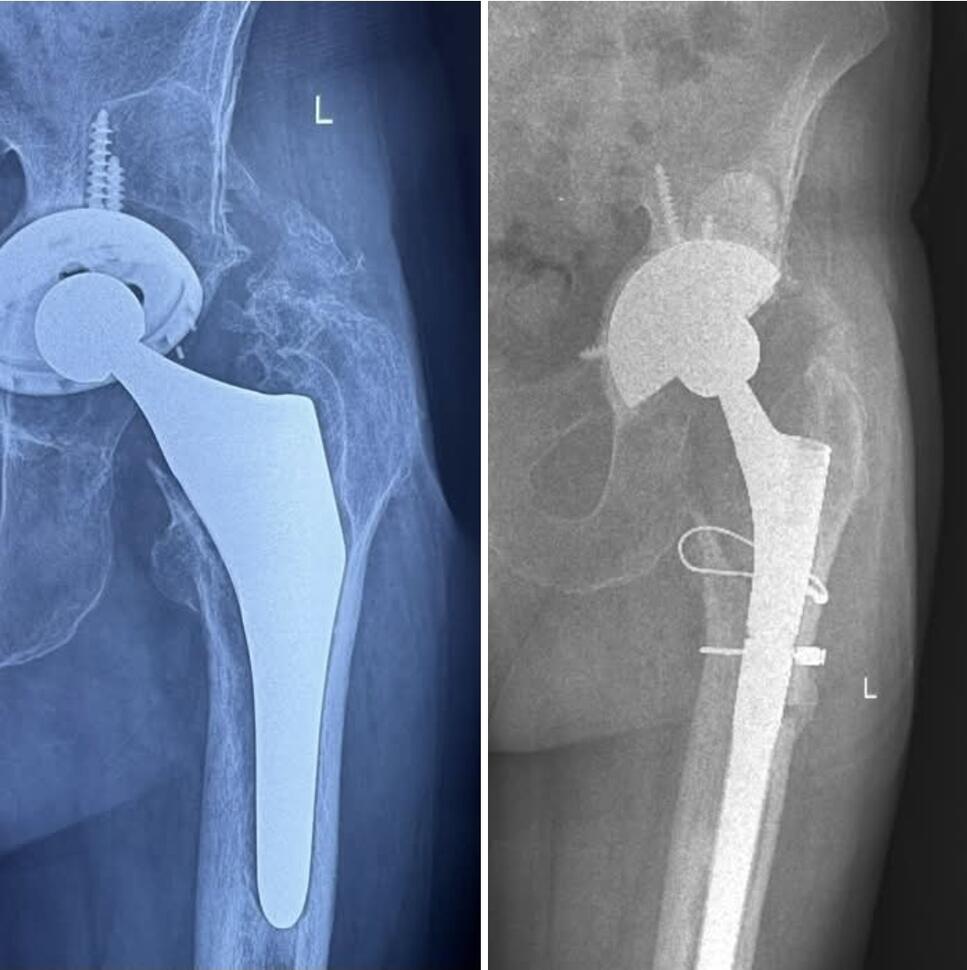

„Domnul Marin, în vârstă de 87 de ani, a venit în cabinetul meu cu dureri intense și un mers aproape imposibil, din cauza deteriorării unei proteze de șold implantate în urmă cu 15 ani.

Am luat decizia de a efectua înlocuirea protezei existente cu o proteză de revizie-Tantal poros (Trabecular Metal) și stem Revitan, iar intervenția a decurs fără complicații. Recuperarea a fost bună, iar la 6 luni de la operație, domnul Marin și-a recăpătat mobilitatea și normalitatea vieții de zi cu zi.